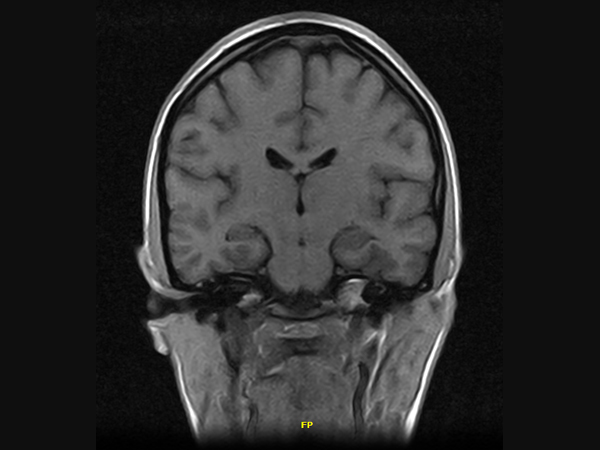

Klinické snímky